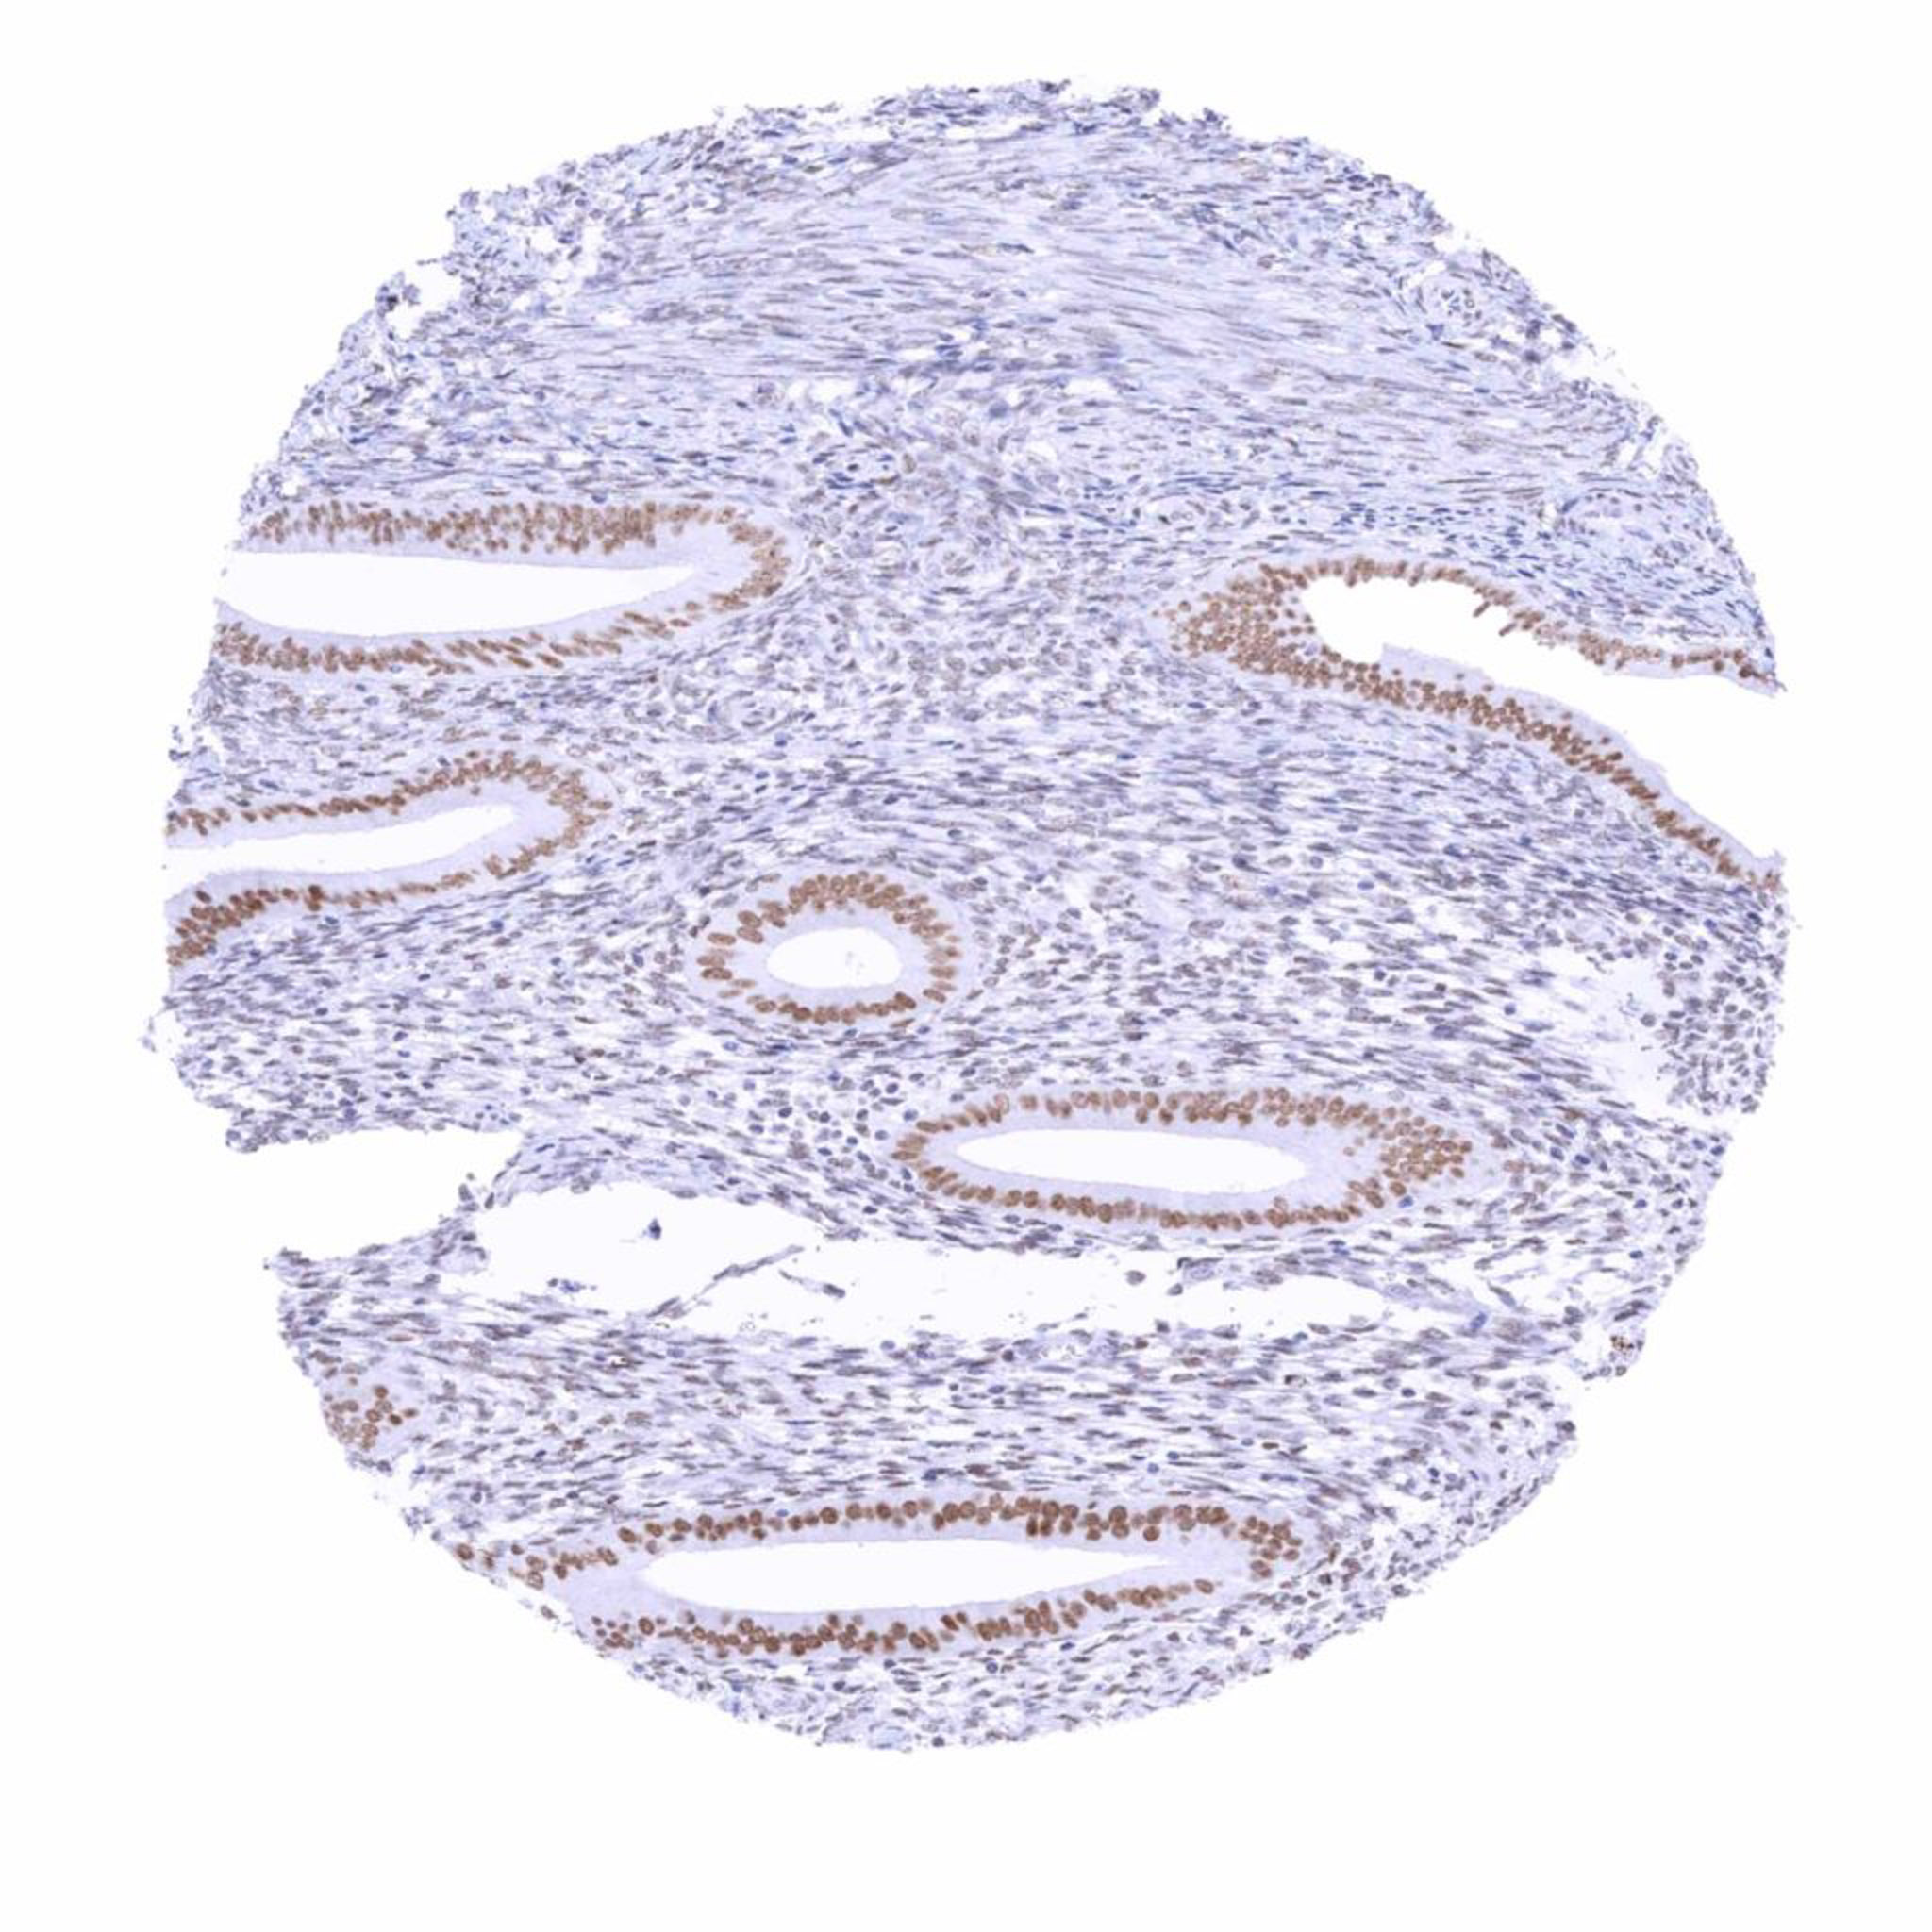

Uterus, endometrium (proliferation) – Moderate nuclear TRPS1 staining of epithelial cells and weak staining of stroma cells